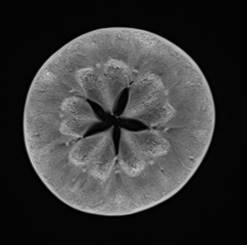

MRT-Aufnahmen eines Apfels

MRT-Aufnahmen von Apfel und Melone